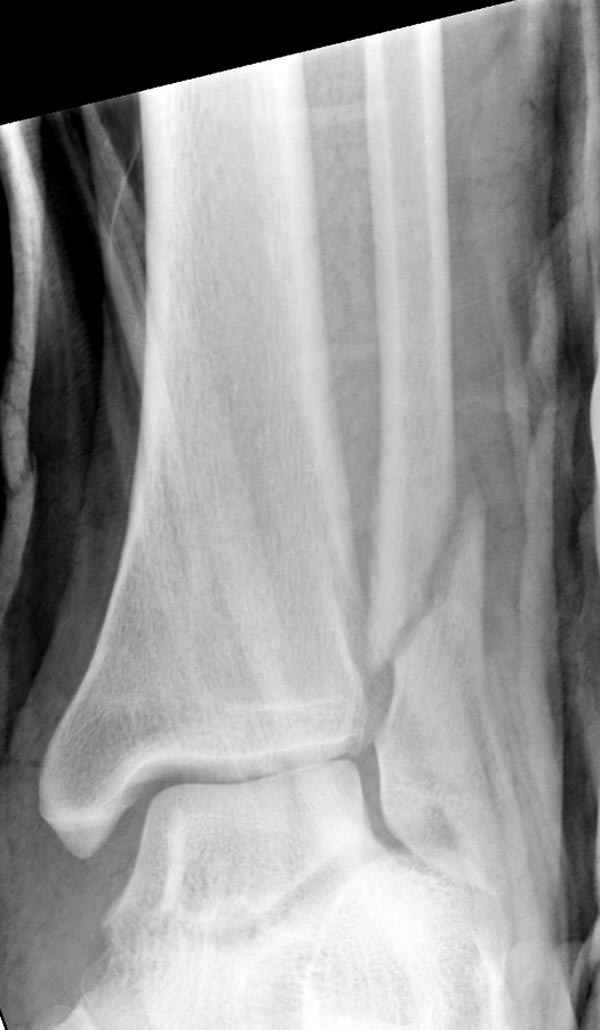

Тему неоднократно разбирали (см. архив), как всегда, недостаточны ренгенологические исследования - кроме прямого и боковых снимков, еще нужна косая ренгенограмма для определения ankle mortise, без мортиз снимка трудно определить высоту и ротацию малоберцовой. (снимки)

Показания для фиксации: укорочения и ротация малоберцовой, особенно обращают внимание на любой подвывих таранной кости: неустраненый подвывих впоследствии приводит к раннему артрозу. Задний край фиксирует тогда, когда перелом составляет около 25% суставной поверхности голеностопного сочленения и смещение более 2мм.

По снимку ваш случай относится к Weber В, фиксацию производят восстановлением длины малоберцовой кости, под ренгеном (ЭП)контролем, для этого я предпочел бы латеральный доступ, остеотомия по линии перелома, удлинение малоберцовой засчет скоса линии остеотомии, компрессия “lag technique”по линии остеотомии и фиксацию провести латеральной пластиной. Отдельный задний доступ, остеотомия по линии перелома, репозиция и фиксация заднего края вашим предпочтительным методом: 3.5мм шурупом с шайбой или пластиной Antiglide Butress

method. При восстановленном суставе, уменьшится медиальная щель, а при Weber В повреждается только передне-нижняя межберцовая связка синдесмоза, повреждение которой приводит к наружной ротации

малоберцовой, но после восстановления всех смещений, связка автоматический приближается к исходному и нет необходимости восстановления синдесмоза.